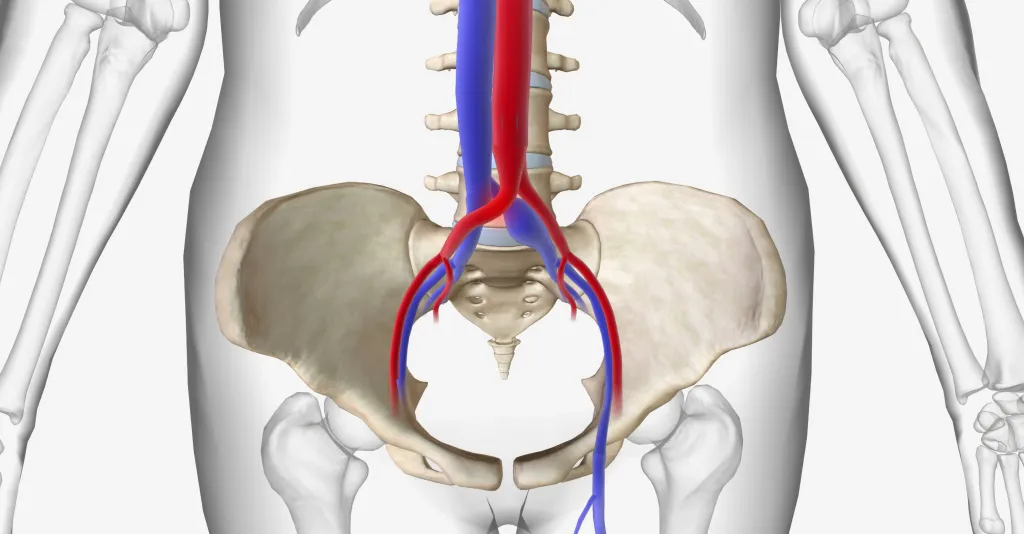

在 May-Thurner 综合征的经典形式中,左侧髂总静脉被相邻的右侧髂总动脉挤压在腰椎上,尽管可能存在多个其他潜在的压迫区域。已报道其他压迫机制,如髂动脉支架、肿瘤、以及前移的腰椎间盘,仅举几例。

May-Thurner 综合征在普通人群中的发病率不一,高达约 25%,在症状性患者中甚至更高。尽管通常在临床上没有症状,但它可能导致单侧水肿甚至下肢血栓形成。其诊断可以使用磁共振、计算机断层扫描 静脉造影或带有血管内超声(IVUS)的侵入性静脉造影。有许多领域需要进一步研究,包括可能具有临床意义的狭窄程度。提出了 50%至 60%范围内的值。

静脉内支架治疗压缩或狭窄段已成为症状性患者的首选侵入性治疗方法。

May-Thurner 综合征:左侧髂总静脉被相邻的右侧髂总动脉挤压在腰椎上